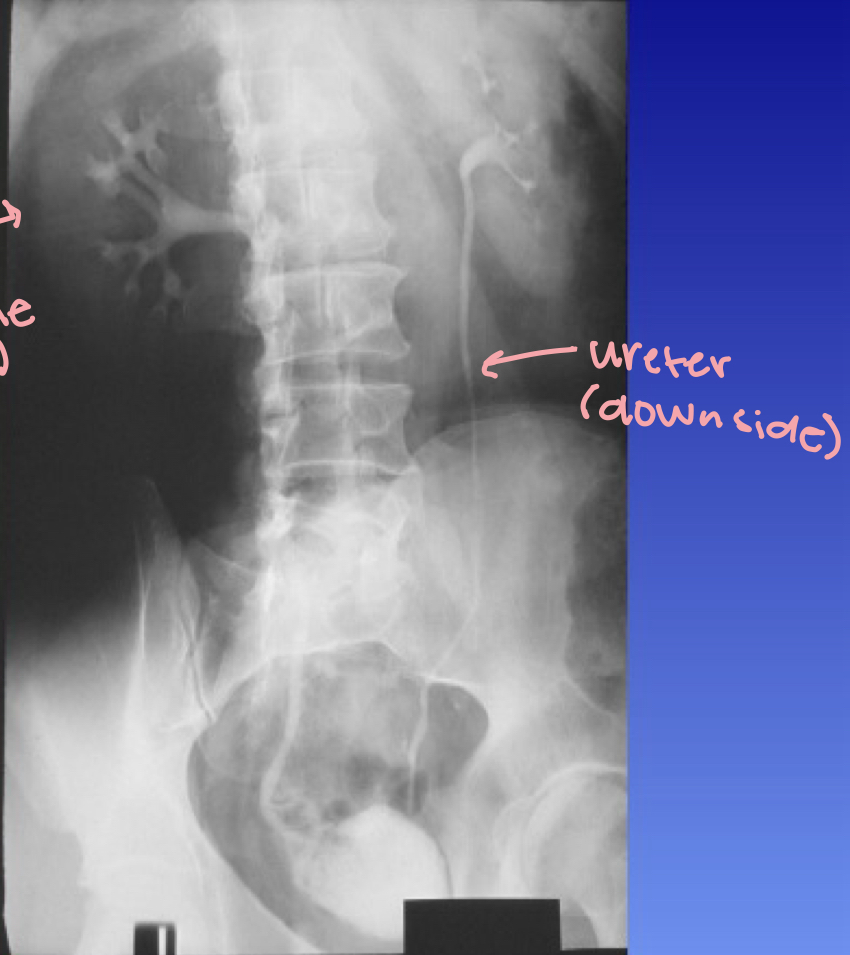

What is this X-ray demonstrating?

IVU posterior oblique